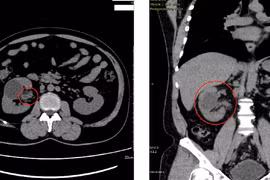

Bị tiểu máu 1 năm nhưng bệnh nhân không đi khám đến khi đái máu, sụt 10kg đi viện thì được chẩn đoán ung thư biểu mô đường niệu phải cắt bỏ thận, niệu quản và bàng quang.

Bị tiểu máu 1 năm nhưng bệnh nhân không đi khám đến khi đái máu, sụt 10kg đi viện thì được chẩn đoán ung thư biểu mô đường niệu phải cắt bỏ thận, niệu quản và bàng quang. Đây là loại ung thư thường gặp, người dân cần chú ý.

Ung thư thận là loại bệnh đứng thứ ba trong ung thư tiết niệu, chiếm 2,8% trong tổng số các bệnh ung thư, lại không có dấu hiệu và triệu chứng rõ ràng ở giai đoạn sớm. Vì thế người dân cần chú ý.

Ung thư thận là kết quả của một số tế bào thận phát triển không kiểm soát, dẫn đến một khối ác tính. Đây là một căn bệnh nguy hiểm, cần được điều trị càng sớm càng tốt.